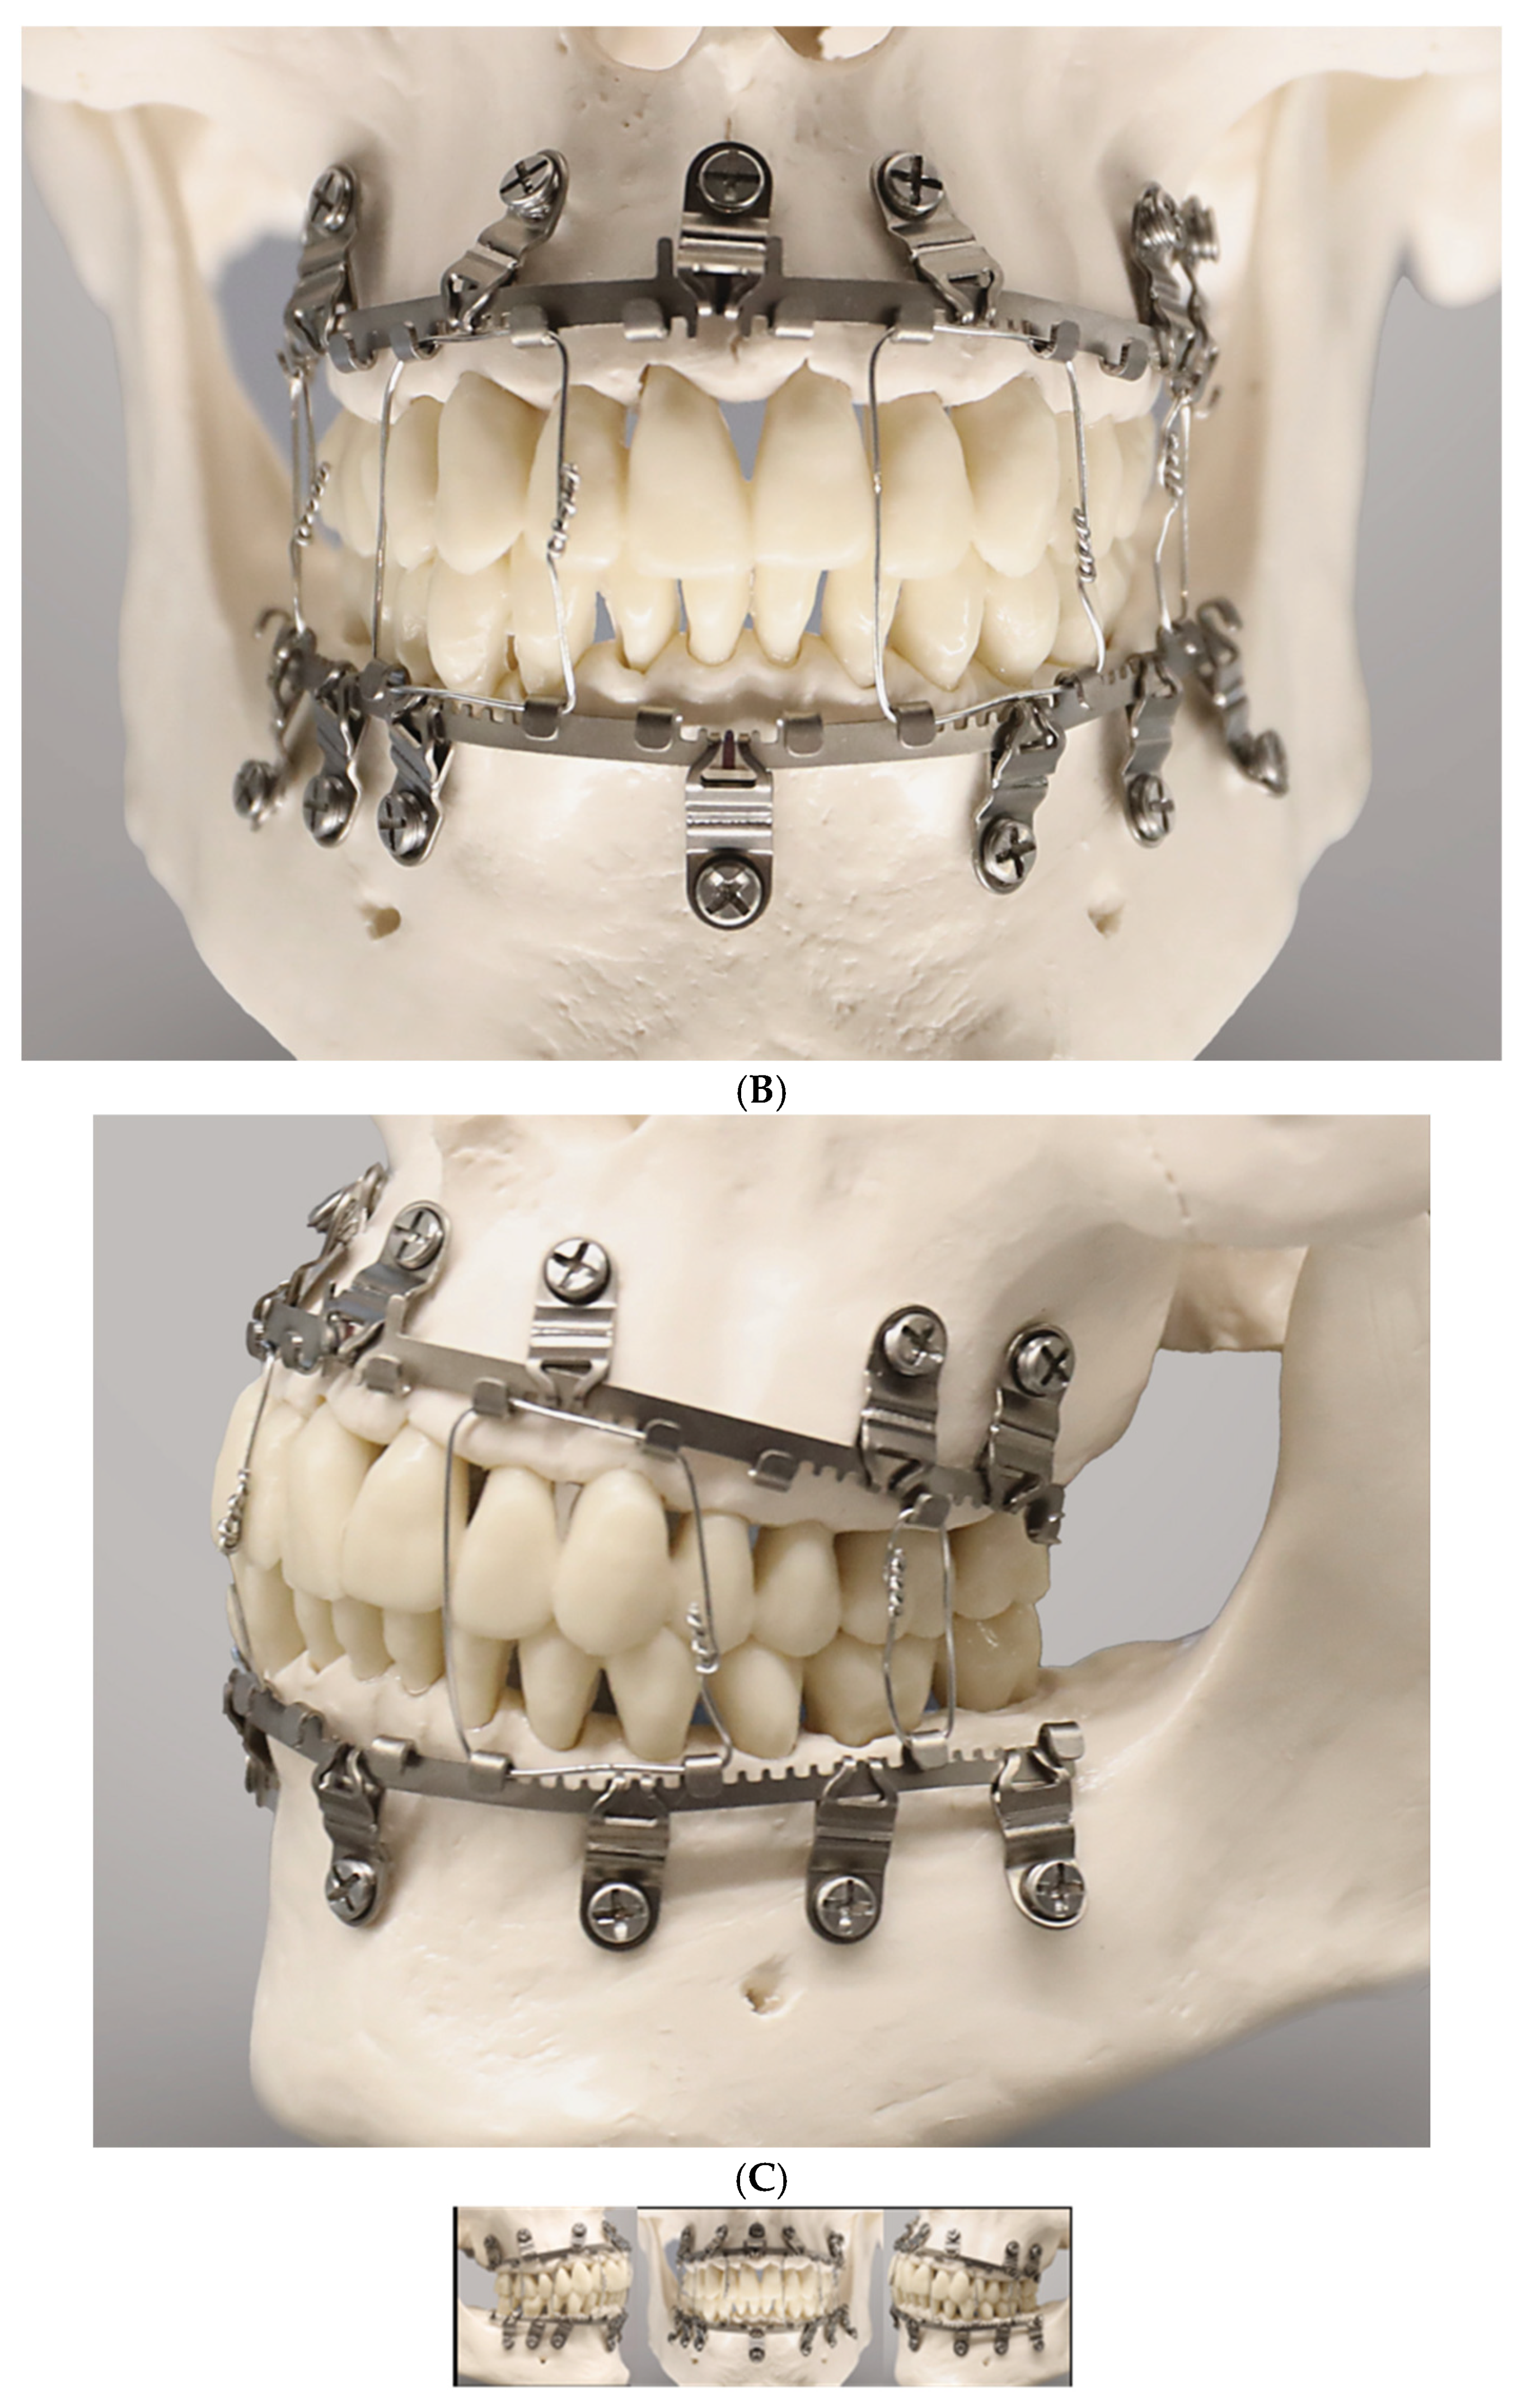

Figure 5.

(A) Full arch assembly of L1 MMF arch bar/slider plates and intermaxillary wire ligatures in a model—right lateral view. The maxillary bar sections above the incisors and premolars as well as the mandibular bar sections below the lower lateral incisors are void of tabs and gaps (‘teeth’); the angulation of the lateral slider plates and montage under tension maintains the purposed interdigitation between their slots and the arch bar rack. Note: suboptimal asymmetrical vertical placement of lower lateral arch bar sections subsequent to in plane bending alongside the free gingival margins and tooth necks (periodontally unfavorable). (B)—frontal view. Angulation of slider plates in upper incisor/canine regions; apart from a midline slider plate the lower incisor and canine region are spared from slider plates accounting for the high risk of tooth root injuries due to narrow interradicular spaces. (C)—left lateral view. The slider plate below the lower canine is not properly engaged in the mating bar rack resulting from a too parallel montage—a flaw—in long-term yielding to forces and potentially hazarding stability. Source/origin: L1 MMF System provided by courtesy of KLS Martin, Tuttlingen, Germany—model montage by C.P. Cornelius.

3.7. L1 MMF System (KLS Martin)

A recent arrival to the league of bone-borne (hybrid) MMF systems is the L1 MMF Device (KLS Martin), consisting of single-edge toothed titanium arch bars and plural slider plates, which are affixed to the dento-alveolar bone with self-drilling locking screws. The present design (Figure 5A–C) corresponds to an optimized or alternate (2nd or V 2.0) version of the device in the United States (US Patent No. 10,470,806 B2—12 November 2019) [12] with changes to the mounting/slider plates (Figure 6). The L1 MMF Device was released to market in North America in 2019 and is currently (2025) awaiting commercial launch in Europe.

This KLS Martin L1 MMF System is made from Titanium and consists of rack-edged arch bars and relocatable slider plates with a 0.5 mm profile. The arch bars come in a “7-hole” and a “9-hole” length with seven or nine slider plates which contain the holes for bone-anchorage with a locking screw. The rack edge of an arch bar contains seven or nine segmental rows of spaced rectangular tabs and gaps which are separated by six or eight wire hooks, respectively. The edge of the central section has an even surface at both sides of a midline indicator (Figure 6). This indicator resembles a trident with two extended outer processes and an inner tab. In the upcoming international market versions, the rack edges will be varied in terms of the total number of wire hooks, their mutual proximity and design of the spaces in between (evenly or regularly jagged by tabs and gaps).

Each slider plate comprises three parts—a coupling portion extending from a main body and a screw-receiving hole (Figure 6 and Figure 7)—building up a front side, an intermediate U-shaped plication and a rear side, which abuts the mucosal tissues.

The coupling portion has a large hourglass-shaped aperture within the front and backside. The narrow neck of the hourglass corresponds to a pair of legs bordering an elongated vertical slot. This configuration provides an improved overview and even insight of the leeway space of the coupling portion. This permits better control of plate maneuverability, adaptation and engagement into the arch bar.

Each section of the arch bar has a single slider plate, which can be slid or shifted in the transverse direction along the row of tabs and gaps within the confines between two wire hooks. The interdigitation of the slot and legs of the plates’ coupling portion with the tabs and gaps (‘teeth’) of the rack edge enables some moveability, so that the plate can be twisted, tipped over and/or angulated.

3.7.2. L1 MMF System—Mode of Application

The application of an L1 MMF bar begins with the selection of an appropriate bar length and shaping it to the patient’s anatomy. If there is no fracture interrupting the dental arch, the center of the bar, indicated by the trident and/or a laser etching, is positioned in the midline of the upper or lower jaw. The bar’s spatial orientation is directed alongside the mucogingival gum line and is intended not to cover the free gingival margins (L1 MMF Technique guide and catalogue, KLS Martin; You Tube Videos—L1® MMF, Technique Guide; L1® MMF, Surgical Technique). The slider plate is then released from its coupling in the trident. The loose slider plate is moved on all three axes to scan the alveolar relief with the screw-receiving hole until an appropriate interradicular space is found.

As soon as a safe location is identified, the leg extensions of the slider plate are seated on the tab of the bar and the anchoring screw is inserted. The slider plates are secured with 2.0 mm self-drilling locking screws of 6 or 8 mm lengths (Figure 5A–C).

The locking mechanism between the screw and slider plate is not yet activated. Prior to activation, the slider plates along the laterally neighboring bar sections are slid sideways into position, engaged into the rack profile and provisionally fastened with screws.

It must be noted that room for up-and-down mobility of the bar would persist if the slider plates were aligned perpendicular and in parallel to the bar unit, since the bar could enter and back out of the leeway spaces inside the coupling portion of the plates, alternatingly. To immobilize the arch bar section, the ‘teeth’ of the rack edges must immutably stack within the slot extension of the slider plates.

A reliable foothold between every two successive bar sections and the associated pair of slider plates can be effectively achieved by fastening the plates in a mutual angular position, pulling the bar teeth into the plate slots.

For a tight anchorage of the remainder of the bar sections towards the molar regions, each following slider plate must be coupled not in parallel but in a diverging angulation to the previous one (Figure 5A,B).

A bar bracing the entire mandibular or maxillary arch will require five mounting/slider plates to hold it in position. At the end, the maximal rigidity of the overall MMF system is leveraged as soon as intermaxillary wire ligatures are applied to the hooks and fully tightened in dental occlusion (Figure 5A–C).

L1 MMF System

The L1 MMF System is designed as a multicomponent system consisting of a fundamental bar unit derived from a conventional Erich arch bar and an ensemble of vertically arranged members, the mounting or slider plates (Figure 11). The rack edge of the bar unit is segmentalized by intermediate wire hooks into consecutive rows toothed with rectangular tabs and gaps. The central segment of the bar unit contains a trident process (Figure 5B and Figure 6) with two outer appendages and an inner rectangular tap formation. The elongated trident in the middle of the bar unit serves to define the midline of the dental arch as well as leveling the bar at an appropriate vertical height.

The rack profiles on either side of the central segment provide transverse guiding lanes for the slider plates.

The slider plates have a two-leg slot extension to snap into one of the continuous rectangular “tab and gap” (=tooth) spacings along with the rack edge in the bar sections, similar to a gear mechanism. The back and front side of a plate’s coupling portion enclose the bar unit like an oval tube (Figure 5A, Figure 6 and Figure 11).

One slider plate is pre-assembled per segment. Therefore, two chained segments are the shortest applicable partitioning of an L1 MMF bar.

An L1 MMF bar unit—anatomically adapted in length and curvature—is applied via the slider plates, which can move transversely. Each plate is brought into a position, in which the screw-receiving hole lies above a safe interradicular space and the two-leg slot is engaged within the rack.

The mechanical interdigitation (=plug connection) between the tooth spacing of the rack and the slider plate leg extension is not a high-precision fit but rather a contact relationship, leaving some degree of flexibility in any direction. The slider plate can be twisted, tipped over or angulated within given constraints along the three rotational axes (Figure 12).